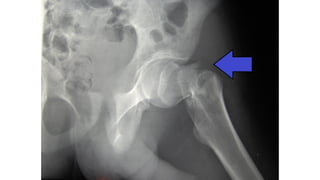

This document discusses femoral fractures, categorized by their location and severity, with classifications such as Garden classification. It outlines the types of fractures, including valgus impacted, non-displaced, partially displaced, and fully displaced, along with their surgical treatment options. Additionally, it briefly describes distal femur fractures, which occur just above the knee joint.